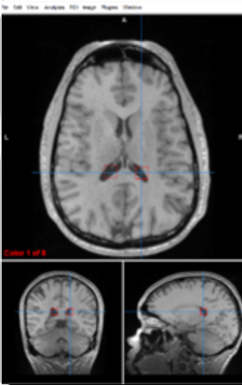

putamen/globus pallidus

regulate voluntary movement, motor planning, and learning